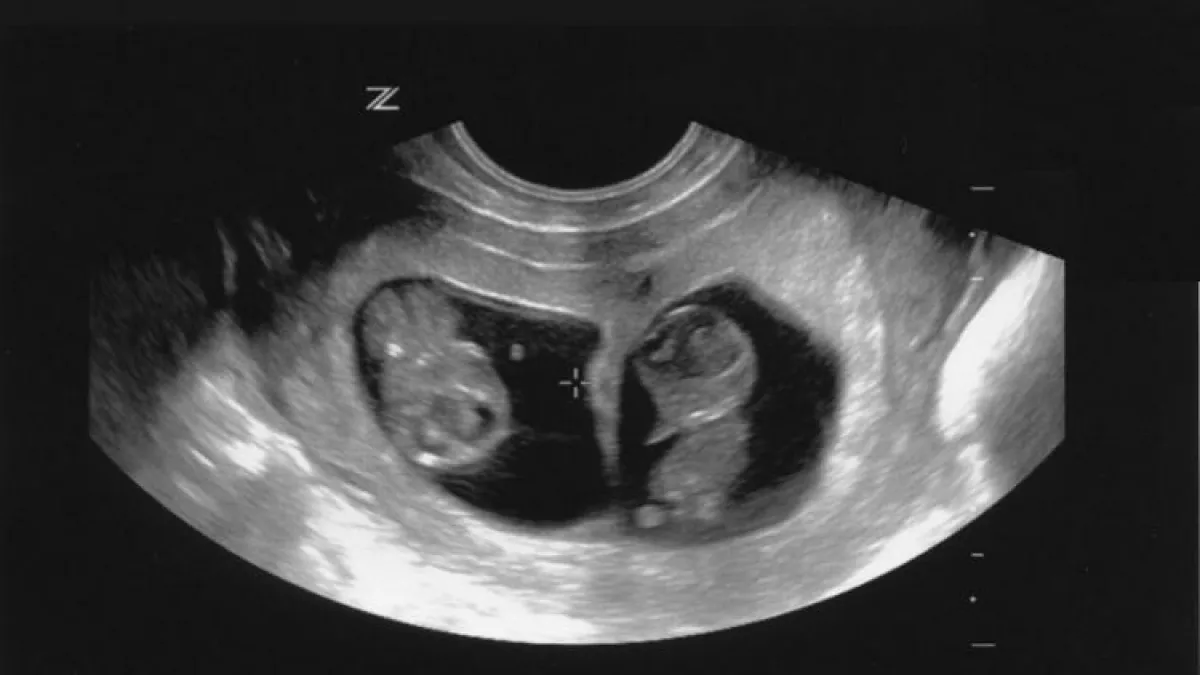

وطبياً، تعرف هذه الحالة باسم "جنين داخل جنين"، "foetus in fetu"، وهي حالةٌ مرضية نادرة جداً، حيث لم يتم الإبلاغ في جميع أنحاء العالم إلا عن 200 حالة مشابهة. وقد تم العثور على الجنين في البطن بنسبة 80% من الحالات المعلن عنها، لكن هناك تقارير تفيد بحدوثه في الجمجمة.

ويعود سبب ذلك إلى عدم اكتمال فصل التوائم، فيبقى أحدهما غير قادرٍ على النمو بشكل ذاتي، ليصبح جزءاً داخلياً من توأمه.